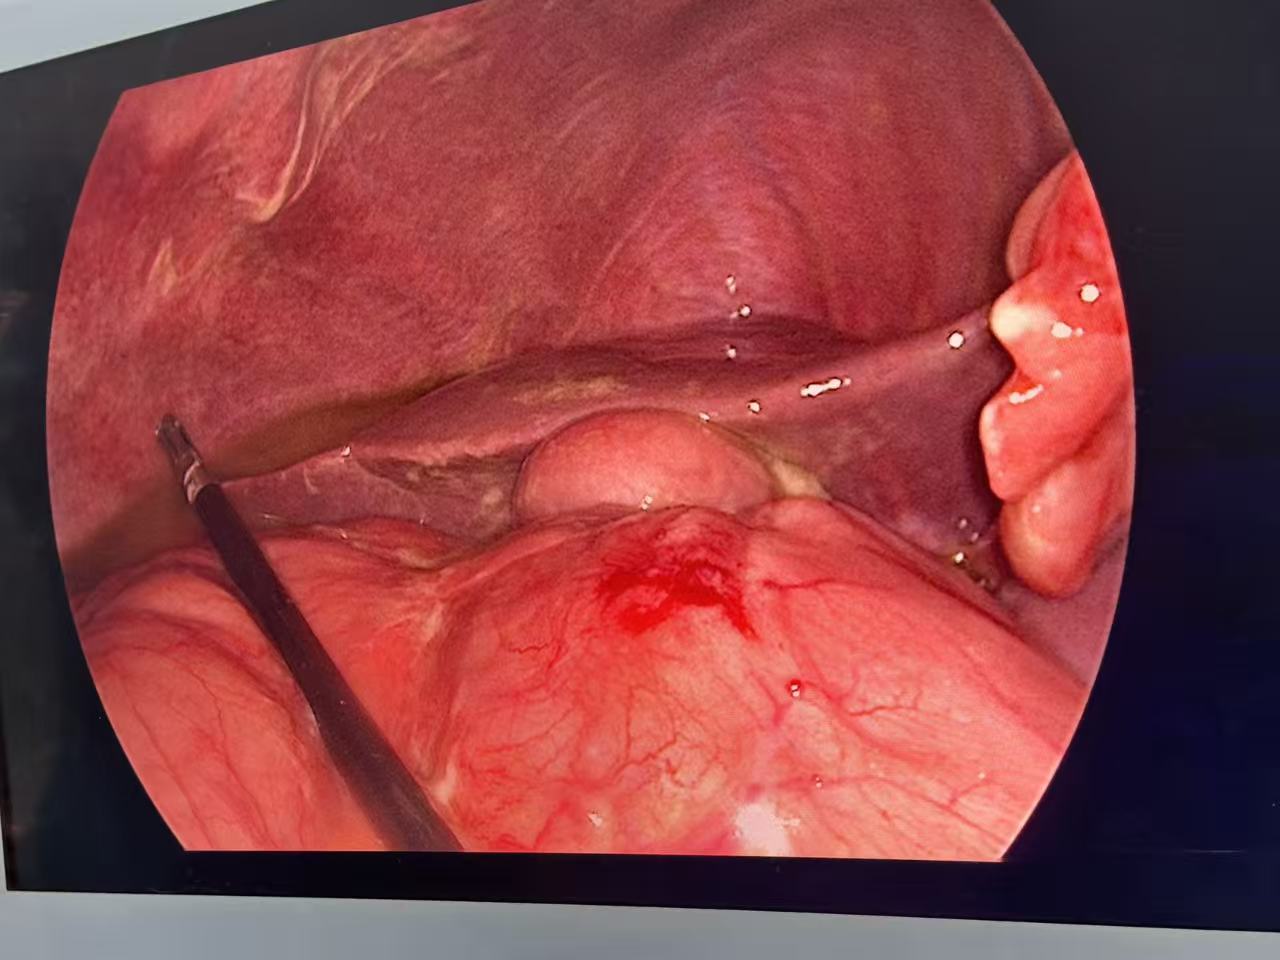

——精准、微创的“管道修复术”

在医疗技术欠发达的年代,治疗穿孔的唯一方法是开腹大手术。而现在,腹腔镜微创手术已然成为治疗消化道穿孔的首选方案。近日,普外科成功为一名消化道穿孔患者实施了腹腔镜修补术,手术仅通过几个0.5-1cm的小孔就完成了穿孔部位的缝合与腹腔清理,患者术后第二天即可下床活动,大大缩短了住院时间。这种手术方式不仅创伤小、恢复快,还能更清晰地探查腹腔内情况,降低遗漏病灶的风险,为患者带来了更优质的治疗体验。

术中探查情况

术中处理穿孔位置